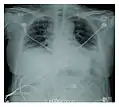

Rapid progression from initial symptoms to respiratory failure is a key feature. An X-ray that shows ARDS is necessary for diagnosis (fluid in the small air sacs (alveoli) in both lungs). In addition, a biopsy of the lung that shows organizing diffuse alveolar damage is required for diagnosis. This type of alveolar damage can be attributed to nonconcentrated and nonlocalized alveoli damage, marked alveolar septal edema with inflammatory cell infiltration, fibroblast proliferation, occasional hyaline membranes, and thickening of the alveolar walls. The septa are lined with atypical, hyperplastic type II pneumocytes, thus leading to the collapse of airspaces. Other diagnostic tests are useful in excluding other similar conditions, but history, X-ray, and biopsy are essential. These other tests may include basic blood work, blood cultures, and bronchoalveolar lavage.

- Acute interstitial pneumonia showing a marked reduction in lung capacity